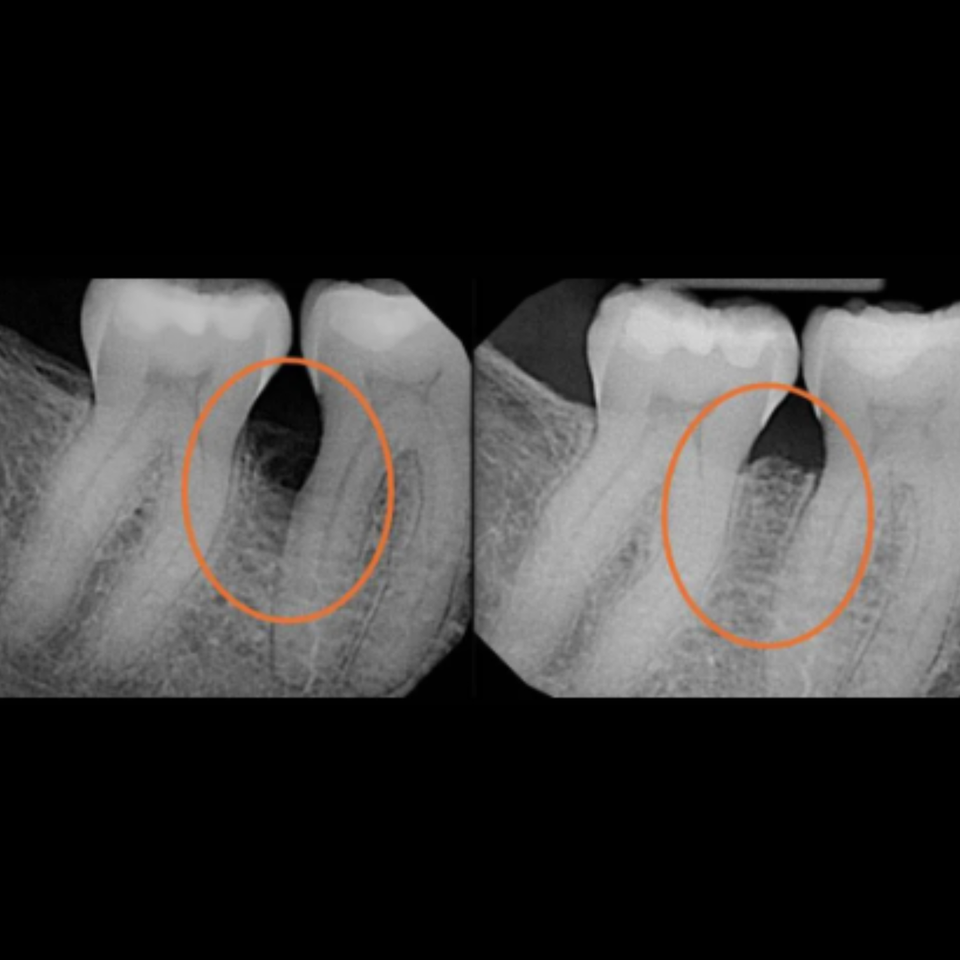

At our practice, we recently helped a patient restore their smile after experiencing a complex dental issue involving a periodontal infection and a root fracture. To fully restore both health and aesthetics, we recommended a comprehensive implant-based solution.

The treatment process included:

• Extraction and Bone Grafting to properly prepare the site for implant placement

• Implant Placement with Soft Tissue Grafting to ensure long-term stability and natural-looking gum contours

• Provisional Implant-Supported Crown to maintain appearance and function during healing

• Final Implant-Supported Crown, custom-designed for strength, beauty, and seamless integration

We are extremely proud of the final result, and most importantly, our patient is now enjoying a healthy, confident smile once again.